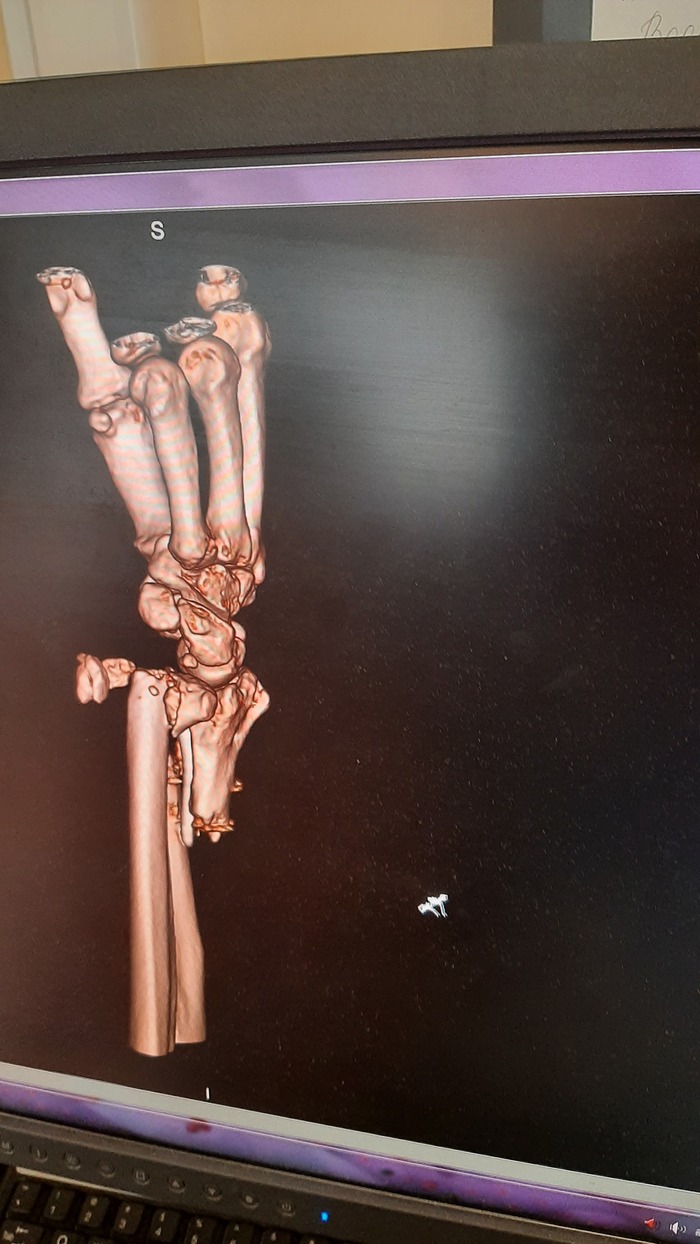

Ну и очень много рентгеновских снимков